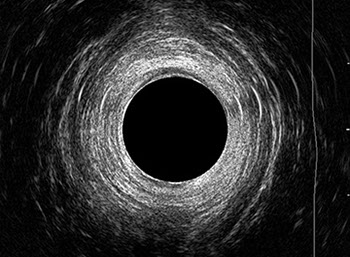

L’ecografia transanale è un esame diagnostico per immagini che consiste nell’introduzione di un trasduttore ad ultrasuoni. Le immagini qualitativamente migliori del canale anale sono ottenute usando un trasduttore rotante, montato in un manipolo rigido, che fornisce un’immagine a 360°. Con le apparecchiature più moderne è anche possibile ottenere immagini tridimensionali.

L’ecografia transanale permette di distinguere la sottomucosa che riveste il canale anale, lo sfintere anale interno, e lo sfintere anale esterno.

Le principali indicazioni all’esecuzione di tale esame sono lo studio dell’integrità delle strutture muscolari nei casi di incontinenza fecale, lo studio topografico dei processi settici perianali (ascessi e fistole) e lo studio dei processi proliferativi epiteliali (carcinoma anale).